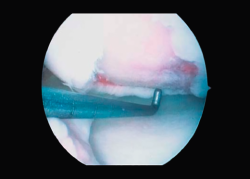

5. The glove is cut along the mark on the instrument table, checking again that the measurement is correct. The dry membrane is trimmed to the size of the lesion. The membrane is placed with the rough zone facing upwards (Figure 9). The cells are received from the laboratory in a sterile jar. Using a sterile pipette, all the cells are placed on the membrane, distributing them well over the entire surface(4) (Figure 10).

6. We have to wait 12 minutes for the cells to penetrate into the membrane (the specific time will be indicated by the membrane laboratory).

7. We then return to the joint, wash it, and carefully dry the lesion bed to ensure the absence of bleeding.

8. The membrane is placed in the lesion and the margins of the former are sutured to the healthy cartilage with Vicryl® 5/0 (Figures 11 and 12).

9. We check that the membrane is well fixed and seal between the stitches with Tissucol® (Figure 13). A waiting period of 3-5 minutes is observed, and the joint is mobilized before closure to check that the membrane does not detach with movement of the joint.